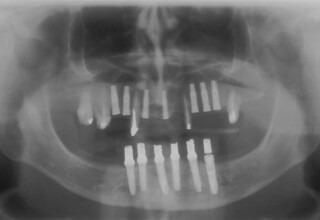

Lower jaw: extractions, direct implant placement and immediate loading (same day) with a transitional bridge.

Upper jaw: Sequential extractions, sequential implant placement and gradual incorporation in the temporary bridge so that the patient was never left without fixed teeth. The aim of the above approach was to have the patient in continuous functional and aesthetic reconstruction, without immediate loading due to anatomical restrictions. Old smiling photos of the patient were used because the natural shape of the teeth was completely lost due to repetitive prosthetic attempts. Tooth relationship and teeth-lip support was transferred to the temporary restorations. Two different transitional bridges were needed to fully estimate phonetics, mastication and esthetics. After the necessary adjustments were finalized, the temporary bridge was used as a guide for the permanent bridges.

Initial

Intermediate

Final